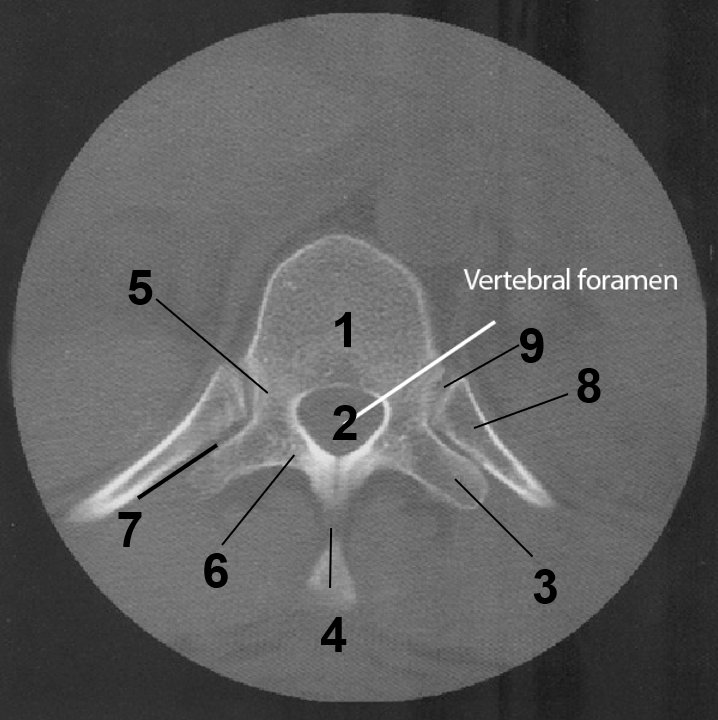

1

Body of thoracic vertebrae

2

Vertebral foramen

3

transverse process